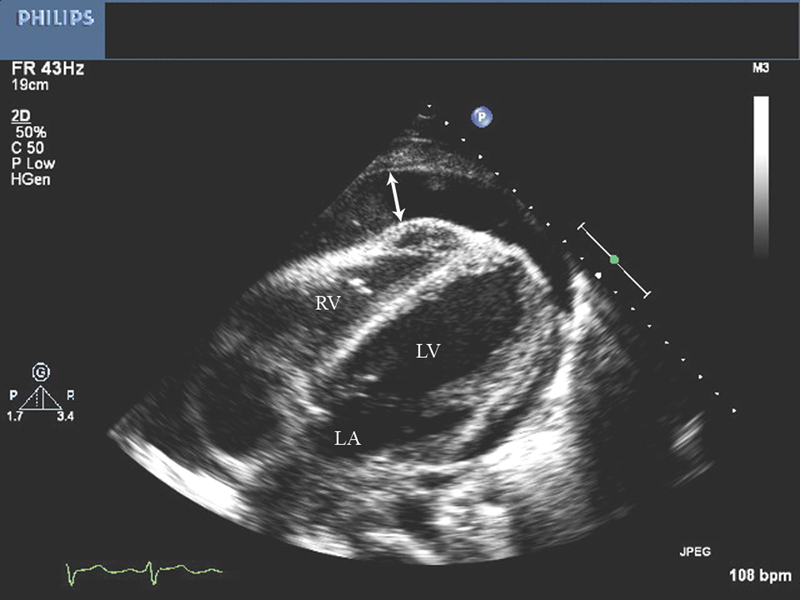

فحوصات تشخيصية لبعض امراض القلب والشرايين التاجية